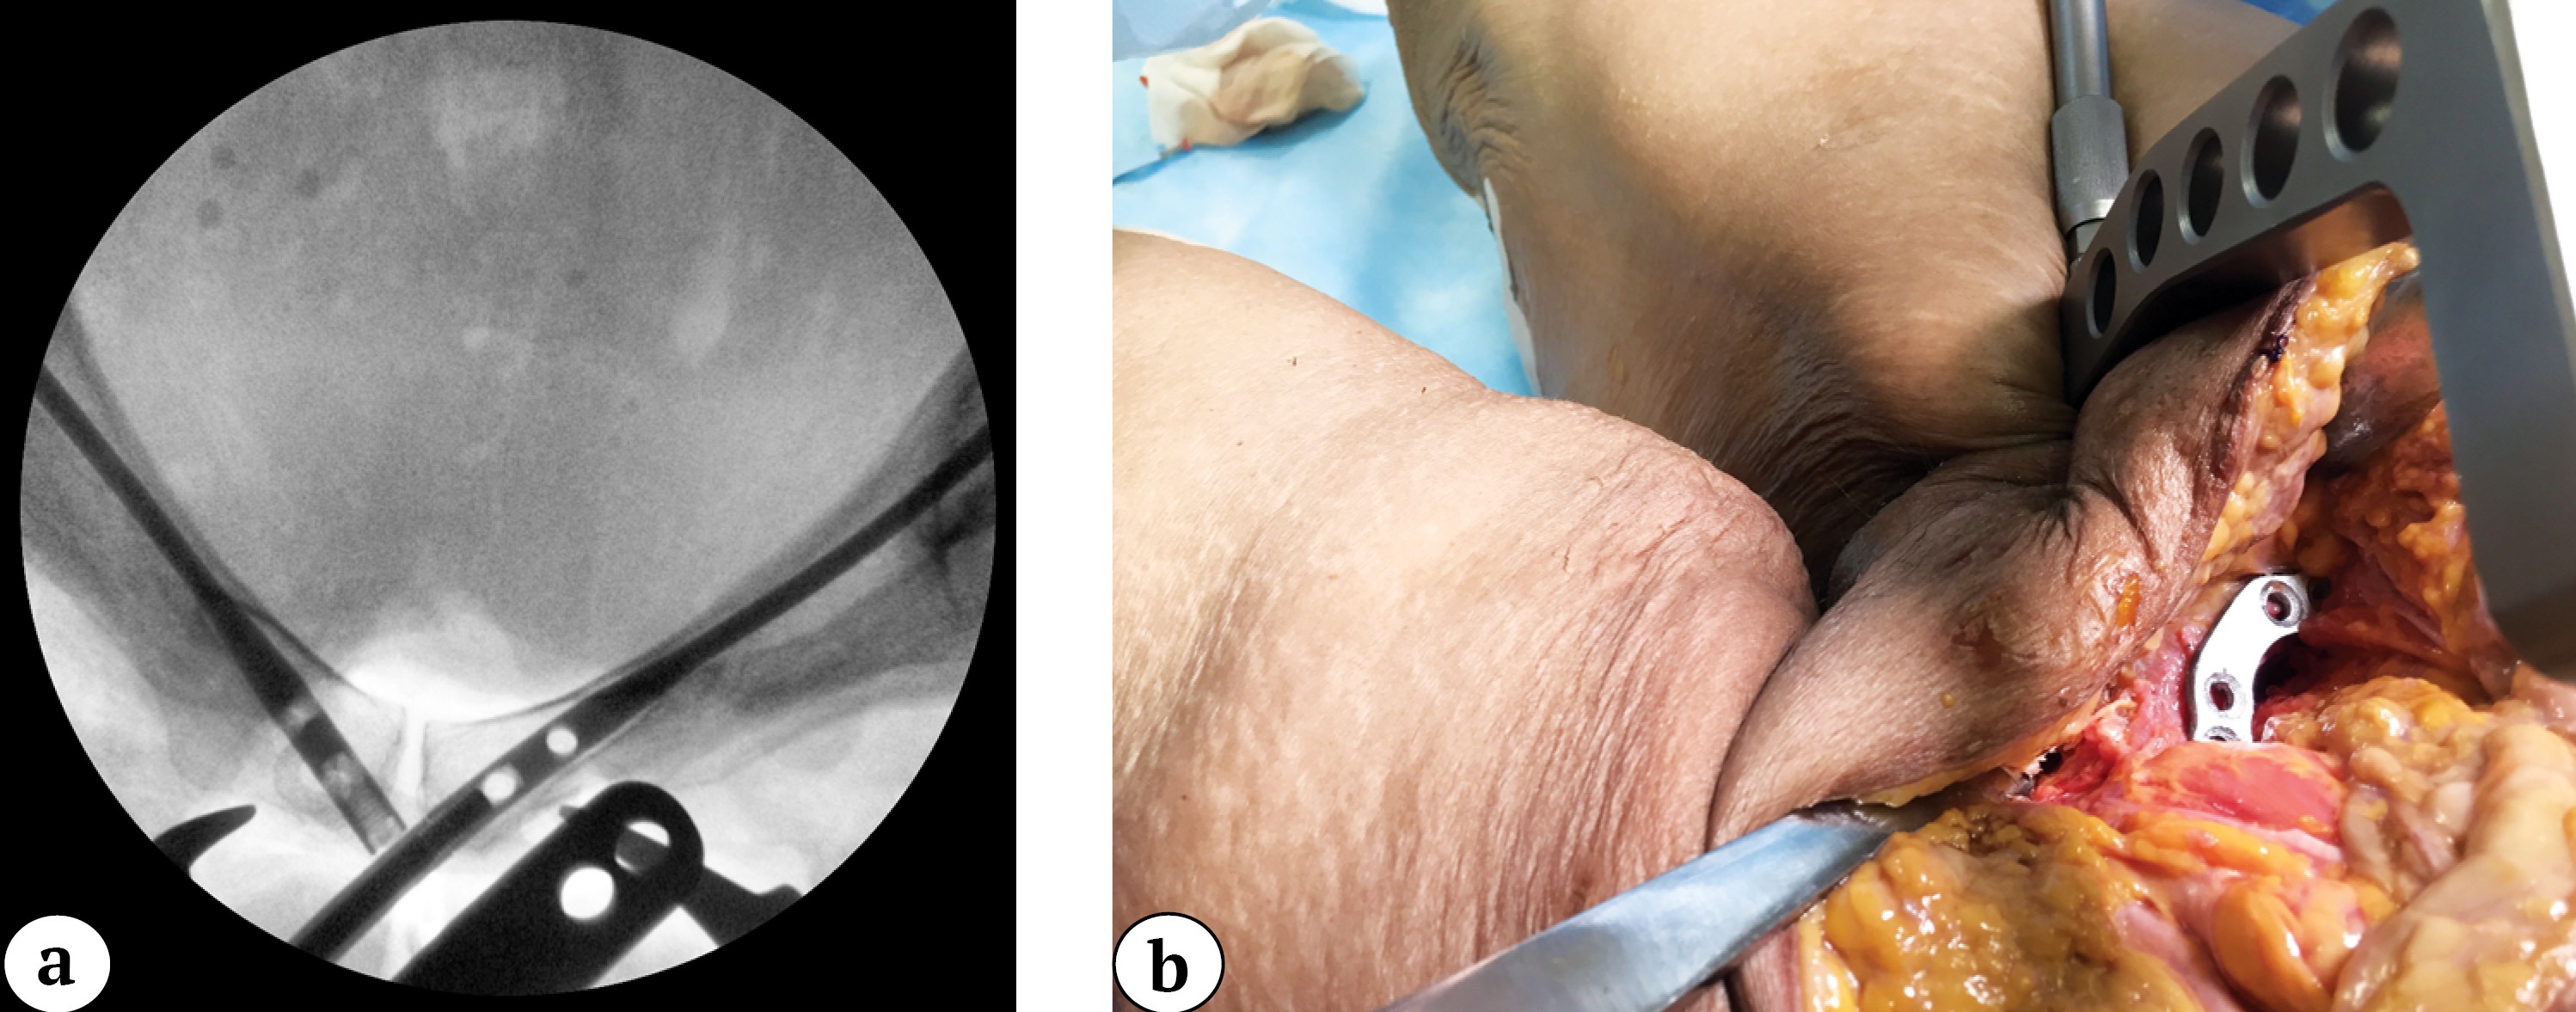

To prevent displacement, the plate was temporarily fixed with a 2-mm wire through the technical hole. A drill sleeve was inserted through the guide handle and aligned with the hole in the plate closest to the symphysis (Figure 4).

Figure 4. Intraoperative outlet view of the pelvis with the guide cannula aligned for nail locking through the plate hole (a); nail locking via the plate hole (b)